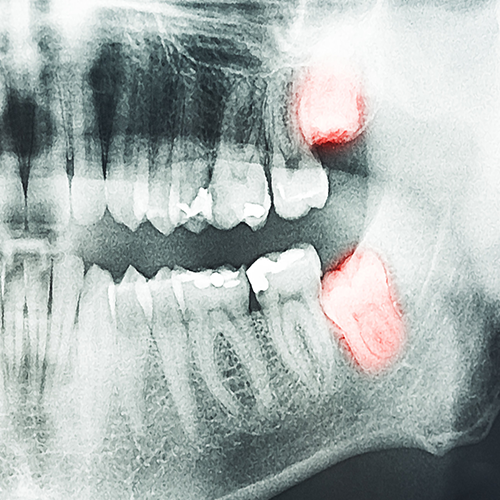

اما در بعضی مواقع در زیر لثه قرار دارند و یا شکسته و آسیب دیده هستند که باید توسط متخصص جراح دهان و دندان جراحی شوند تا بتوان آنها را خارج کرد.

دندان های عقل اغلب به طور غیر طبیعی رشد می کنند و گاهی اوقات به دندان های مولر دوم فشار می آورند. این می تواند به مولرهای مجاور آسیب هم برساند. دندان های مجاور نیز ممکن است نامرتب شوند ، که این امر بر الگوی گزش تأثیر می گذارد.

وقتی الگوی گزش غیرطبیعی می شود ، استرس بیش از حد روی عضلات و مفاصل فک وارد می شود. این مال اکلوژن ممکن است برای اصلاح نیاز به درمان ارتودنسی داشته باشد.

یک کیسه دندان عقل را در داخل استخوان فک احاطه کرده است. اگر دندان عقل کشیده نشود ، این کیسه می تواند پر از مایع شود و کیست ایجاد کنند. کیست های فک می توانند بسیار دردناک باشند و باعث آسیب به استخوان فک ، دندان ها و اعصاب اطراف شوند.

اگر به مشکل کیست زود رسیدگی نشود ، در نهایت جراح دهان و دندان برای درمان این عارضه ، ممکن است جراح نیاز به برداشتن مقداری از بافت و استخوان داشته باشد.

دندان عقل نهفته می تواند همراه با درد فک ، عفونت باکتریایی و تورم ، باعث ایجاد حفره در مولرهای همسایه شود.

هنگام مراجعه به دندانپزشک ، آنها برای برداشتن دندان عقل آن را ارزیابی می کنند. گاهی ممکن است برشی در لثه ایجاد شود و به جراحی بیانجامد تا دندان کامل در معرض دید قرار گیرد تا به برداشتن آن کمک کند. در برخی موارد ، ممکن است برخی از استخوان های اطراف آن لازم باشد برداشته شود و سپس دندان شکسته شود تا بتوئان آن را خارج کرد.